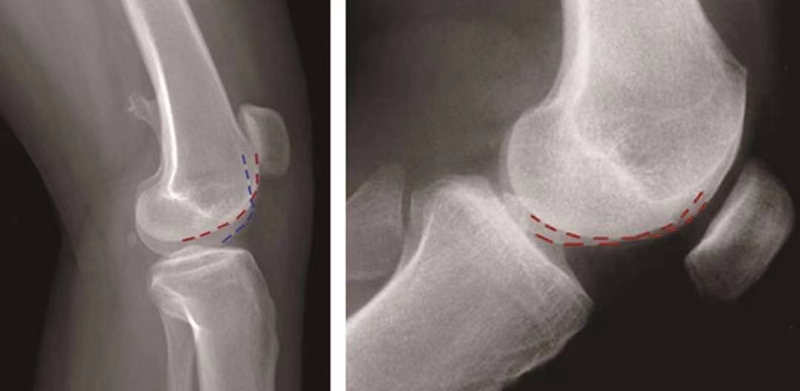

(3)股骨滑车发育不良的分型:

1996年,D.Dejour和B.Le Coultre提出了更准确的股骨滑车发育不良的四种分型(图14):

图14 股骨滑车发育异常分型 A型:交叉征;B型:交叉征+突起征;C型:交叉征+双线征;D型:交叉征+突起征+双线征